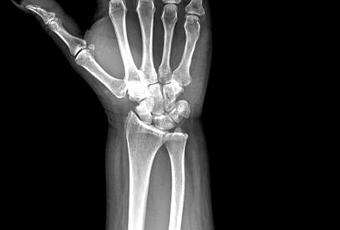

RADIOGRAFIAS AP Y LATERAL DE MUÑECA

Hallazgos:

– De lo observado de radio y cubito, sin evidencia de lesiones líticas, blásticas o perdidas de la contigüidad. Varianza cubital negativa. Alineación entre el 3er metacarpiano y radio, alterada.

-Llama la atención en proyección AP, la sobreposición de el trapecio y trapezoide. Resto de huesos del carpo, metacarpos y falanges, sin evidencia de lesiones blásticas, líticas o perdidas de la contigüidad.

-Las articulaciones radiocubital, cubitocarpianas, intercarpianas, metacarpofalángicas e interfalángicas, con amplitud respetada, sin evidencia de alteraciones.

-Tejidos blandos, con aparente aumento de la densidad y grosor a nivel de eminencia tener, resto con adecuada densidad, con grosor y morfología.

OPINIÓN RADIOLÓGICA:

EN EL PRESENTE ESTUDIO RADIOGRÁFICO, APARENTE LUXACIÓN DEL TRAPECIO EN PROYECCIÓN AP.

APARIENCIA CUBITAL NEGATIVA

PÉRDIDA DE LA ALINEACIÓN ENTRE 3ER METACARPIANO Y RADIO.